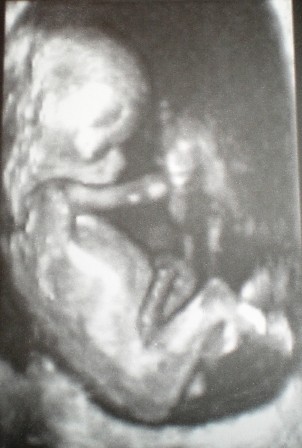

kahaa- sliczne malenstwo

a oto moja slodycz- 12 tc

• 12t0d..JPG

12t0d..JPG

50,6 KB · Wyświetleń: 115

• 12tc..JPG

12tc..JPG

62,8 KB · Wyświetleń: 122

• 12tc-3D..JPG

12tc-3D..JPG

51,3 KB · Wyświetleń: 120